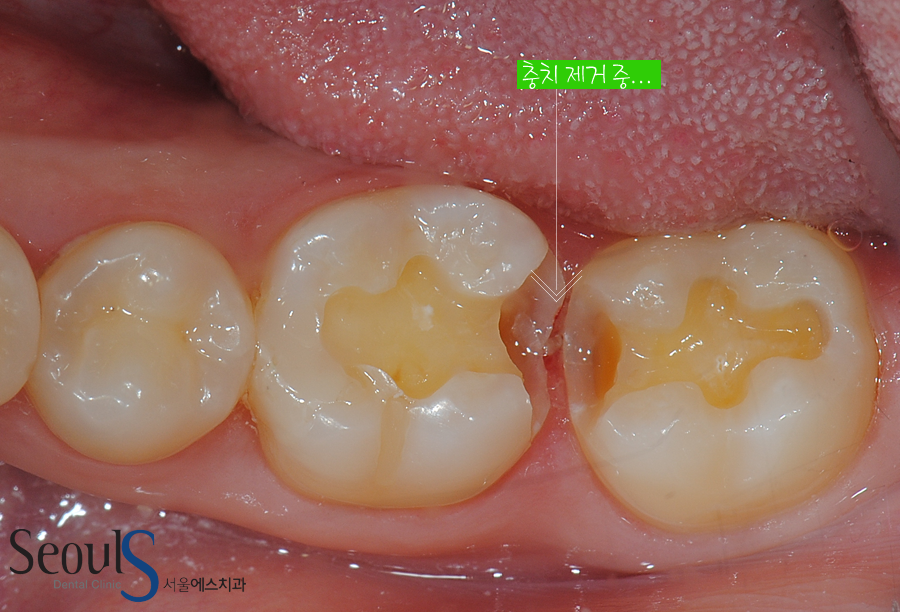

화살표로 표시한 부분, 치아 사이에 음식물이 껴서

충치가 진행되고 있습니다

충치 제거 중…

치아 속 충치를 제거하고 있습니다

충치가 치아 속으로 진행 되고 있는 모습이고 옆 치아도 충치가 진행되고 있습니다

양쪽 치아에 동시에 충치가 진행되고 있습니다